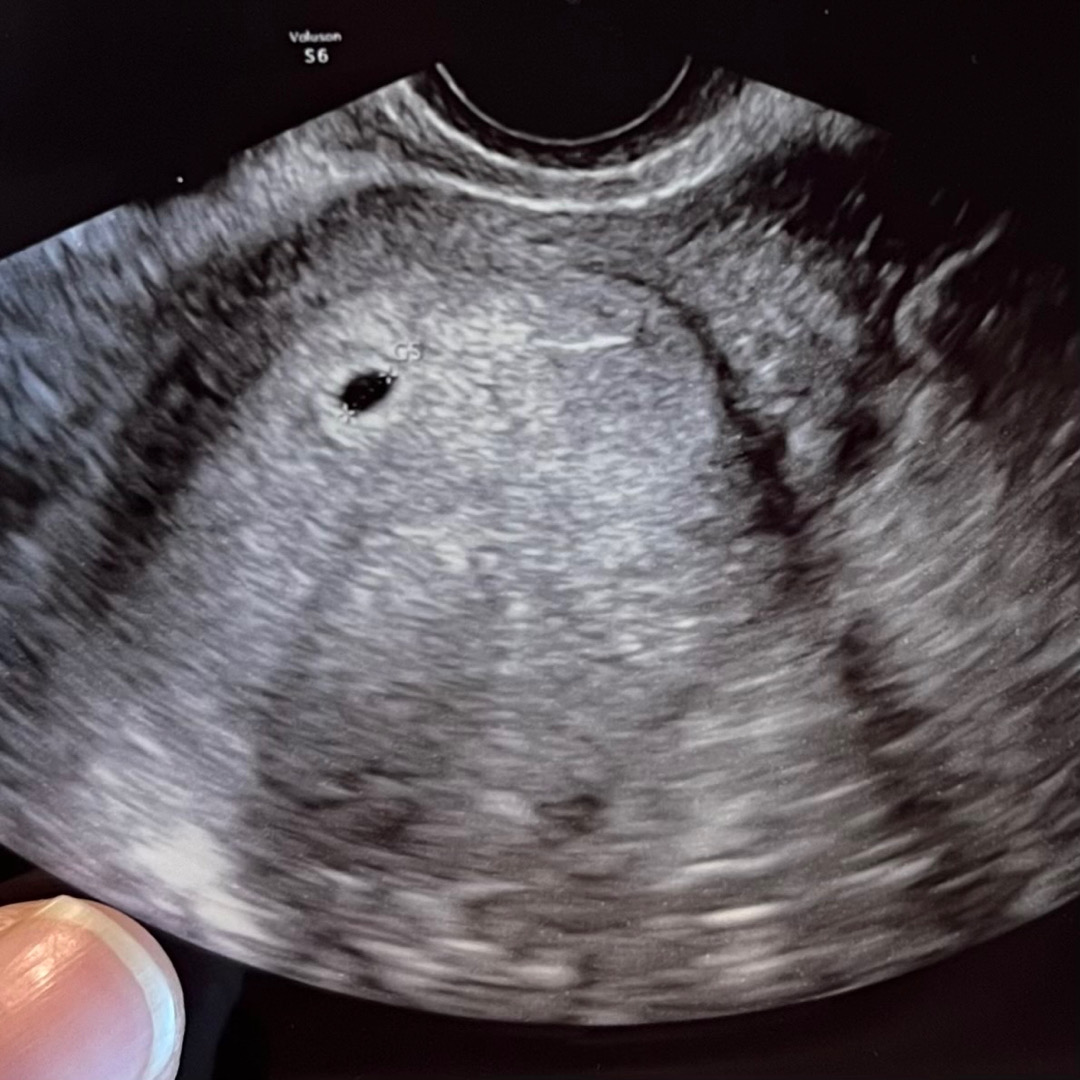

4주 4일 아기집 보고 왔어요!!

저도 드디어 이 글을 올리네요😭 이틀 전부터 역전 시작되어서 오늘 방문했더니 아기집 생각보다 크게 잘 보였어요 ㅠㅠㅠ 선생님도 생각보다 크다며 배란 계산했을 때랑은 다르긴 한데 문제 없다고 하시더라고요! 4.5mm라니... 넘나 작고 소중해.... ㅜㅜ 지금 사진 방향엔 없지만 직접 볼때는 난황도 살짝 보여서 다음 주에 한 번 더 가기로 했어요 :) 그 때 가면 심장소리 들을 수 있을까요?😭 벌써 눈물날 것 같은데 네이버주수 기준으로는 4주 4일인데 지금 크기로는 5주 2일 예상된대요! 첫째 중기유산으로 보내주고 1년 지나 계획 하자마자 잘 찾아와준 아가.. 너무 맘고생 하고 간절하게 기다린만큼 더 소중하네요❤️ 그저 감동에 기쁨... 너무 기분좋네요😆😆